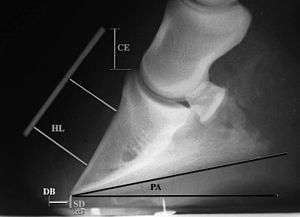

Radiographs

Radiographs are an important part of evaluating the laminitic horse. They not only allow the practitioner to determine the severity of the episode, which does not always correlate with degree of pain,[1] but also to gauge improvement and response to treatment. Several measurements are made to predict severity. Additionally, radiographs also allow the visualization and evaluation of the hoof capsule, and can help detect the presence of a lamellar wedge or seromas.[1] The lateral view provides the majority of the information regarding degree of rotation, sole depth, dorsal hoof wall thickness, and vertical deviation.[1][16] A 65-degree dorsopalmar view is useful in the case of chronic laminitis to evaluate the rim of the coffin bone for pathology.[1]

- Radiographic measurements

Several radiographic measurements, made on the lateral view, allow for objective evaluation of the episode.

- Coronary Extensor Distance (CE): the vertical distance from the level of the proximal coronary band to the extensor process of P3. It is often used to compare progression of the disease over time, rather than as a stand-alone value. A rapidly increasing CE value can indicate distal displacement (sinking) of the coffin bone, while a more gradual increase in CE can occur with foot collapse. Normal values range from 0–30 mm, with most horses >12–15 mm.[1]

- Sole Depth (SD): the distance from the tip of P3 to the ground.

- Digital Breakover (DB): distance from the tip of P3 to the breakover of the hoof (dorsal toe).[1]

- Palmar angle (PA): the angle between a line perpendicular to the ground, and a line at the angle of the palmar surface of P3.

- Horn:Lamellar Distance (HL): the measurement from the most superficial aspect of the dorsal hoof wall to the face of P3. 2 distances are compared: a proximal measurement made just distal to the extensor process of P3, and a distal measurement made toward the tip of P3. These two values should be similar. In cases of rotation, the distal measurement will be higher than the proximal. In cases of distal displacement, both values will increase, but may remain equal. Therefore, it is ideal to have baseline radiographs for horses, especially for those at high-risk for laminitis, to compare to should laminitis ever be suspected. Normal HL values vary by breed and age:[1]